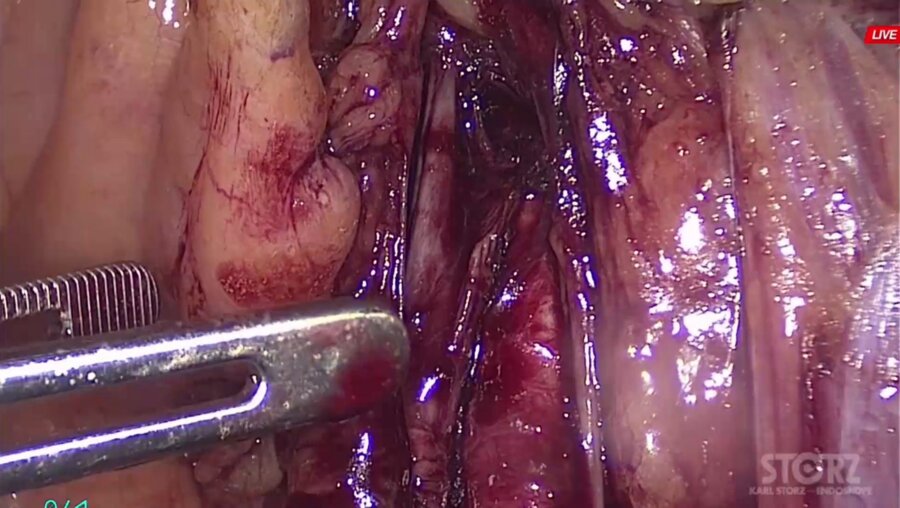

Рак предстательной железы